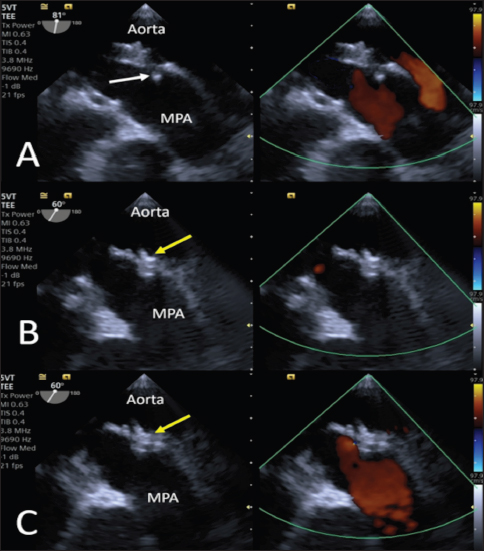

Anesthesia was induced and maintained as previously described (Bagardi et al., 2022) and perioperative intravenous amoxicillin (22 mg/kg) was administered. The dog was placed in right lateral recumbency on a fluoroscopy table (C-arm: Siemens Cios Select Siemens Healthcare), and the area over the right femoral artery was clipped and prepared for surgery. The patient was monitored with transesophageal echocardiography (TEE; Probe: 5VT, Siemens Healthcare), which allowed optimal visualization of the ductus and its measurements (MDD 1.2 mm, ampulla diameter 3.8 mm, and length 4.4 mm), which confirmed the choice of the device (Fig. 3).

Fig. 3. Intraoperative TEE showing PDA and its measurements (MDD: 1.2 mm; ampulla diameter: 3.8 mm; length: 4.4 mm) and the flow from the aorta to the pulmonary artery (MPA) on CFM Doppler (Dual-mode).

Fig. 5. Intraoperative TEE. (A) The first disc is released into the pulmonary artery (yellow arrowhead). (B) The central and proximal discs are positioned inside the ampulla (yellow arrowhead). (C) No residual flow is visible on CFM (Dual-mode) examination, and no flow obstacles are present in the pulmonary artery.